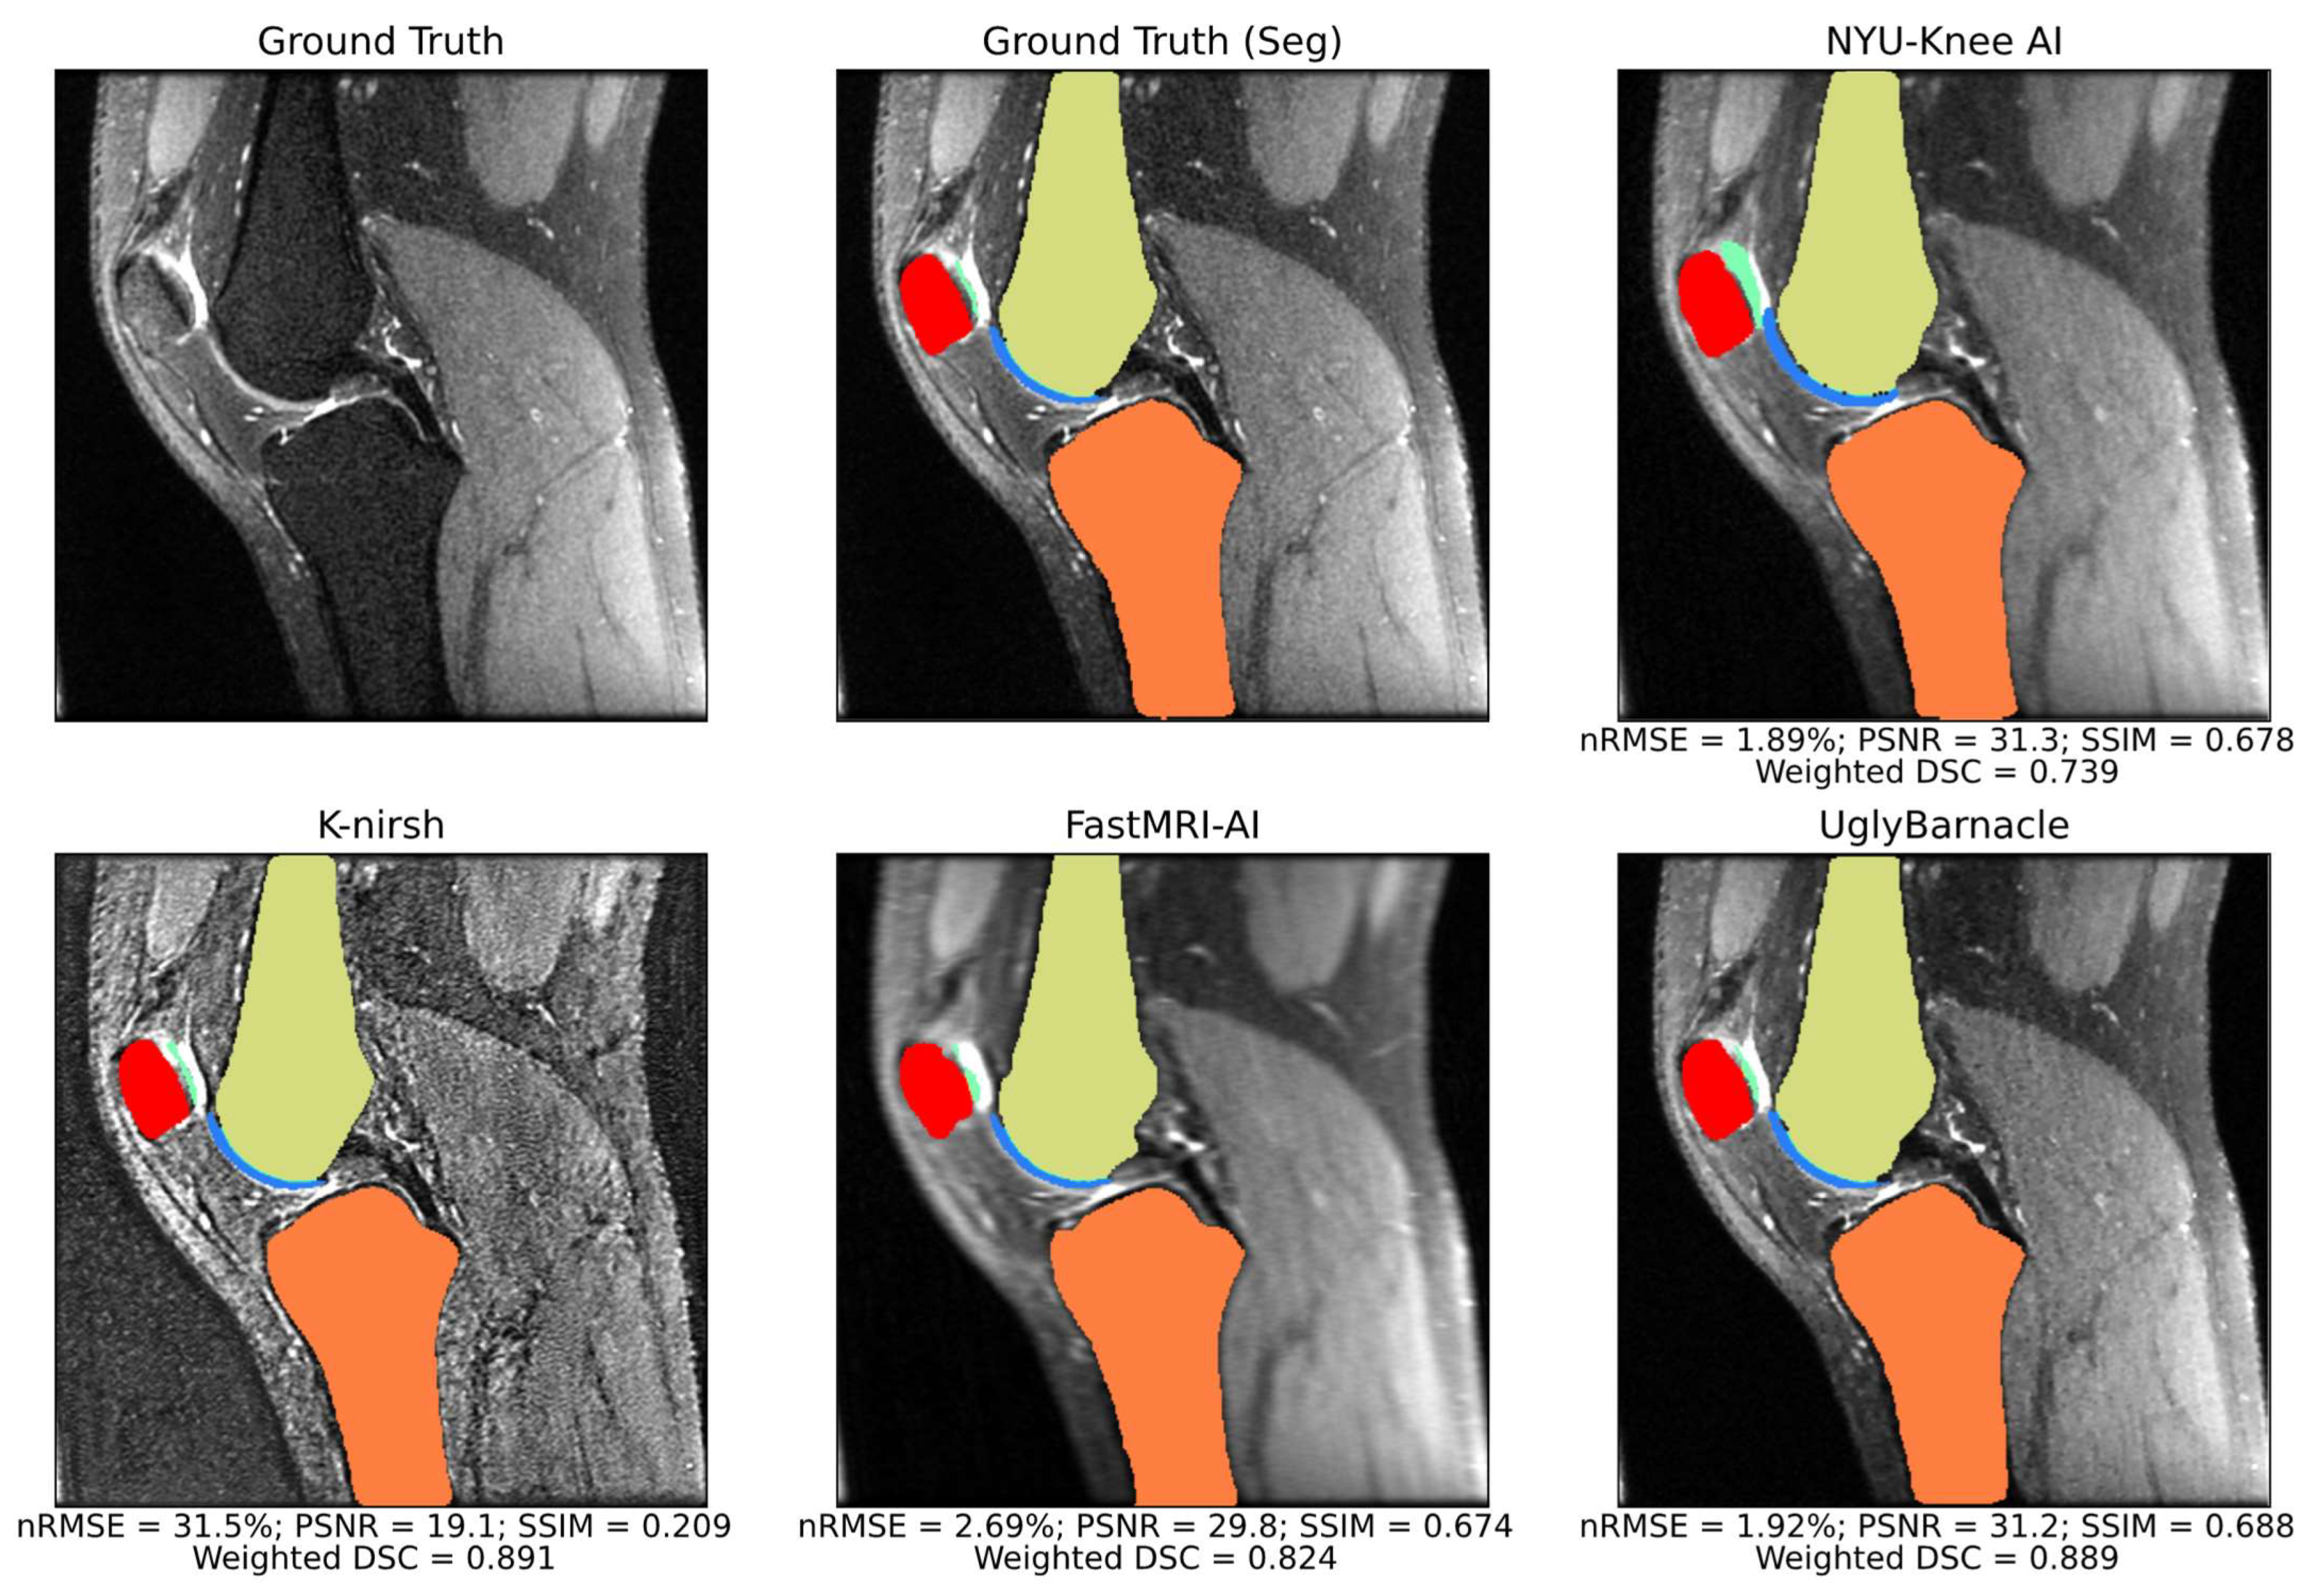

Example sagittal slices of intermediate pipeline reconstruction outputs are shown in Figure 6, with corresponding reconstruction metrics. NYU-Knee AI and particularly UglyBarnacle produced intermediate reconstruction outputs with strong fidelity to ground truth, recovering fine details lost to aliasing. On the other hand, K-nirsh yielded an image with more distinct tissue boundaries, but with noise and pixel intensity distributions that clearly differed from the ground truth. Complete metrics of reconstruction performance are shown in Table 3.

3.3. Comparison of Reconstruction and Segmentation Performance

Example slices of predicted segmentations, overlaid on intermediate reconstruction outputs, are shown for all four teams alongside ground truth in Figure 7. For each reconstruction metric, and for each of the top 4 performing pipelines, weighted DSC was plotted against the reconstruction metric in Figure 8, with Pearson’s correlation coefficients being calculated for each pair. The highest correlation coefficient in this study was between nRMSE and weighted DSC for the NYU-Knee AI submission, at 0.284, with all other correlation coefficients being substantially lower. This indicates that, at the absolute best, there was a weak correlation between segmentation and reconstruction metrics, and in most cases, there was a negligible or even slightly negative correlation between the two.

Figure 6. Intermediate pipeline reconstruction outputs for each of the top 4 submissions in an example sagittal slice, as well as ground truth, with reconstruction metrics displayed for the volume including the visualized slice. For this volume, UglyBarnacle delivers the highest quality reconstruction, followed closely by NYU-Knee AI, recovering sharpness and many fine details lost to aliasing during 8× Poisson undersampling. K-nirsh delivers an intermediate reconstruction that was poor by standard reconstruction metrics, but perceptually, made boundaries between tissues much more distinct and perhaps easier to segment. This is likely due to K-nirsh fine-tuning the reconstruction and segmentation networks in an end-to-end manner, unlike other top submissions.

Figure 7. Sagittal slice segmentations overlaid on intermediate pipeline reconstructions, with reconstruction and segmentation metrics for the volume including the slice displayed. Background anatomy slices were thus blurrier for some teams than for others, as different teams had different quality intermediate pipeline reconstruction outputs. In this example, segmentation quality was strong for all top submissions, with only some overestimation of cartilage thickness from the NYU-Knee AI pipeline being apparent. K-nirsh maintains a slight edge over UglyBarnacle in reconstruction metrics for this volume.